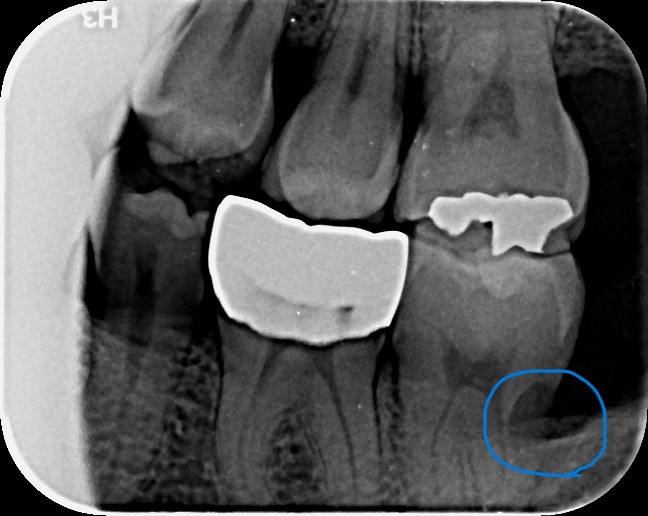

나만의 해우소

거의 모든 이민자들에게 가장 골치 아픈 일은 병원에 가는 일일 것이다. 네이티브가 아니라면 어지간히 해...